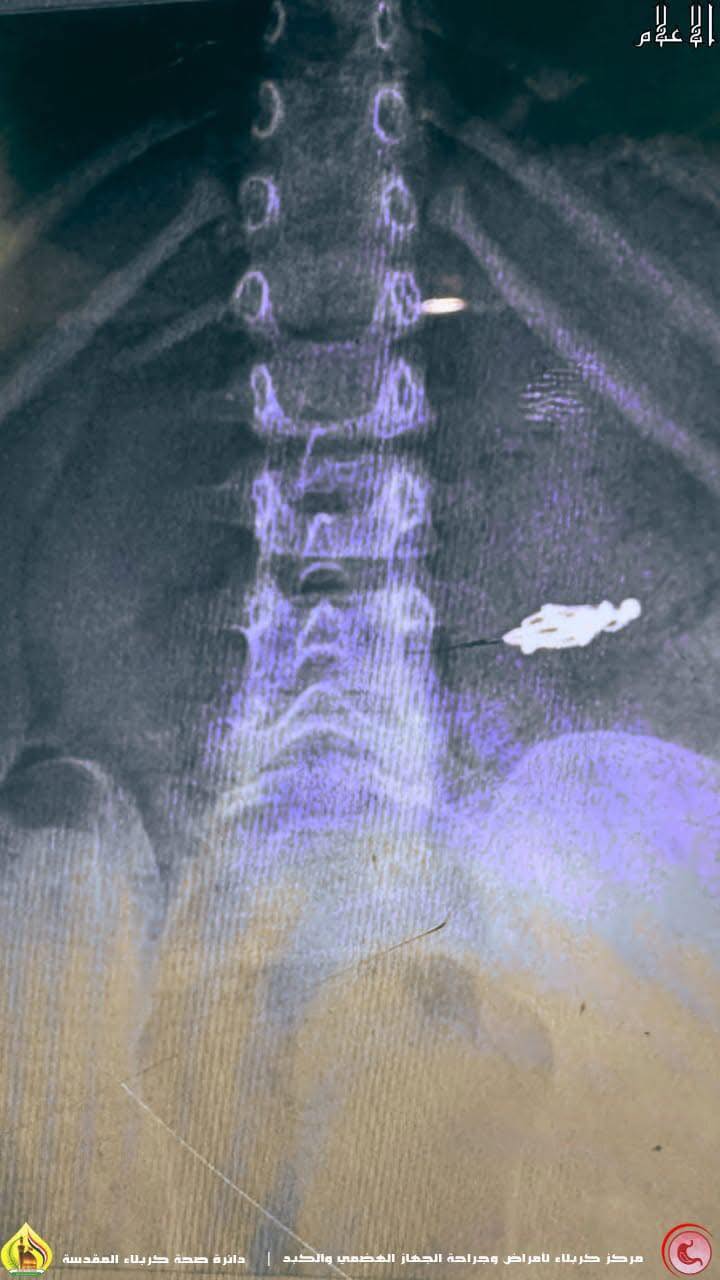

اعلنت دائرة صحة كربلاء ان عملية طارئة ناجحة دامت نحو نصف ساعة تقريباً شهدها مركز كربلاء لأمراض وجراحة الجهاز الهضمي والكبد ، مساء امس الجمعة ، وكانت لطفلة صغيرة عمرها 3 سنوات ، إبتلعت ( حلق إذن) .

وقال رئيس الطاقم الطبي والصحي للعملية ، إختصاصي دقيق بأمراض الجهاز الهضمي والكبد ، الدكتور أحمد هاشم عباس لوكالة نون الخبرية ، أن " الطفلة ، وصلت لطوارئ المدينة الطبية برفقة ذويها عند الساعة الخامسة من مساء اليوم ، وهي تشكو إبتلاع جسم غريب ( حلق أُذن ) كان قد إستقر في منطقة المعدة ، مما سبّب لها ألم في البطن ، وعند نقلها لمركزنا خضعت فوراً لعملية عاجلة بالمنظار لإزالة الجسم الغريب ، كُللت بالنجاح دون حدوث مُضاعفات ، ليتم بعدها إرجاع الطفلة الى الردهة بصحة جيدة.